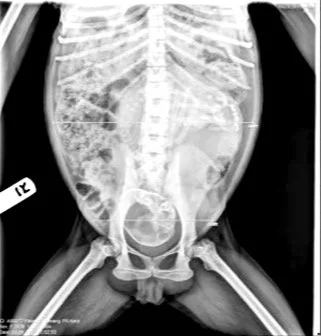

Figure 2. Kera’s obstetric abdominal x-ray.

Kera’s abdomen was prepared by shaving and a thorough scrub. Bedside ultrasound scan confirmed an empty uterus (positive endometrial stripe) and therefore excluded a current pregnancy. Socks were placed over her hands and feet for the purpose of thermoregulation. Kera was then positioned on the operating table in dorsal recumbent and draped exposing the entire abdomen, in the event that conversion to laparotomy was required. Insertion of a urinary catheter was avoided due to the altered location of the urethra in primates, within the anterior vaginal wall, making catheterisation very challenging. We also decided against uterine instrumentation for the purposes of manipulation. Again, this was due to the small female primate reproductive tract (vagina, endocervical canal and uterus), which would be associated with high risk of injury.